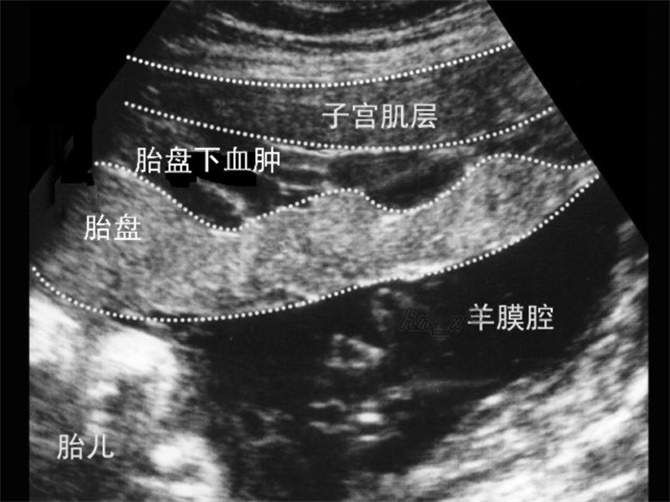

胎盤早剝超聲診斷

胎盤早剝血腫超聲